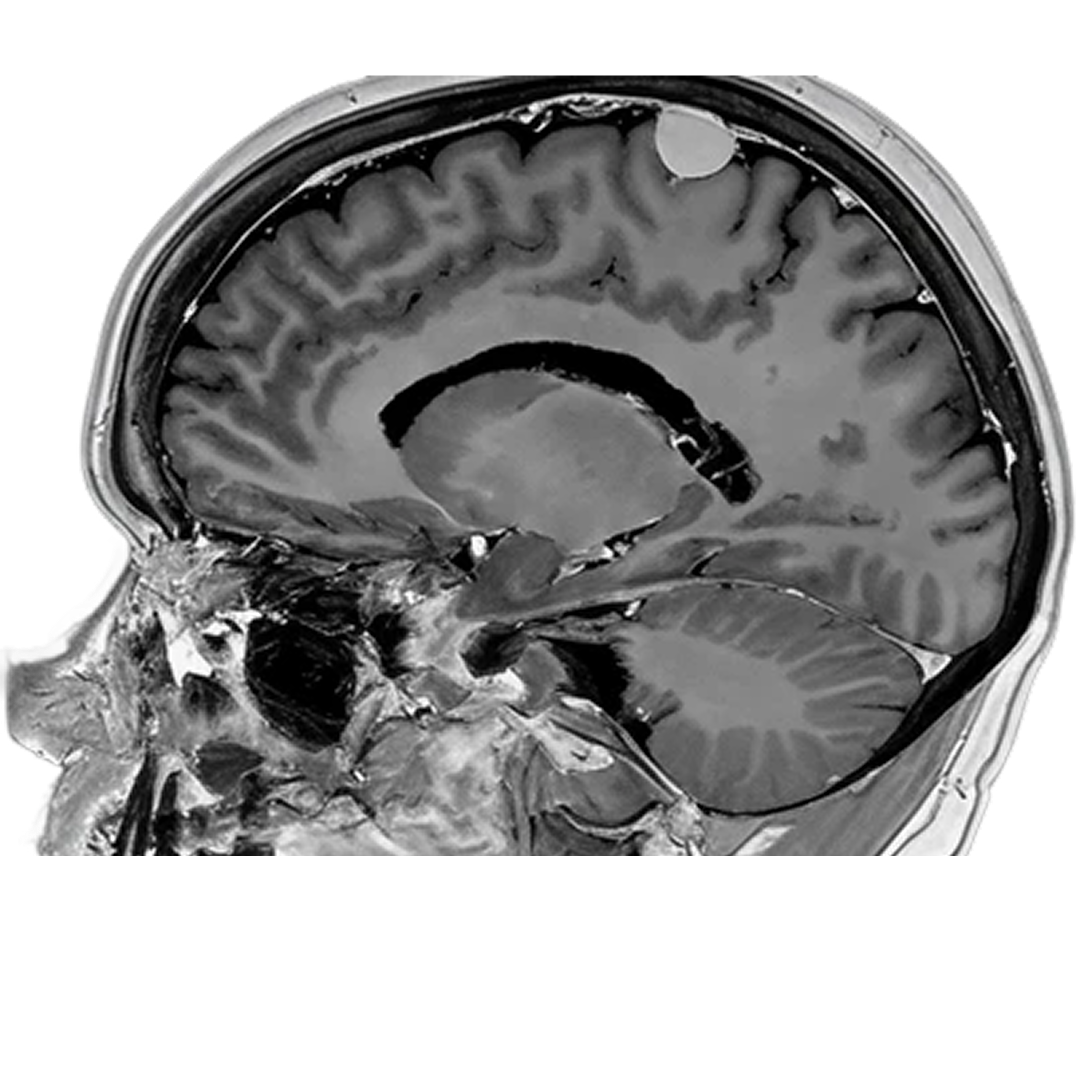

3D T1

1.5T

3D MPRAGE

1.0 x 1.0 x 1.0mm

5:45

0.5T

3D SPGR

1.1 x 1.1 x 1.1mm

5:30

3D FLAIR

Tumor (T1+c)